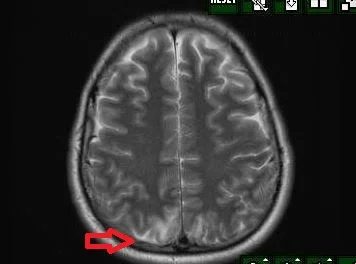

What do you see on the MRI?

Our patient had PRES( posterior reversible encephalopathy syndrome) which was first described in 1996.  The image of the MRI shows edema posteriorly on the T2 weighted MRI.  The reason for PRES in this case was autonomic dysreflexia secondary to spinal cord injury.  In patients with spinal cord injury above the T6 level there is an imbalance of sympathetic discharge since sympathetic control of the splanchnic vascular bed is no longer functioning.